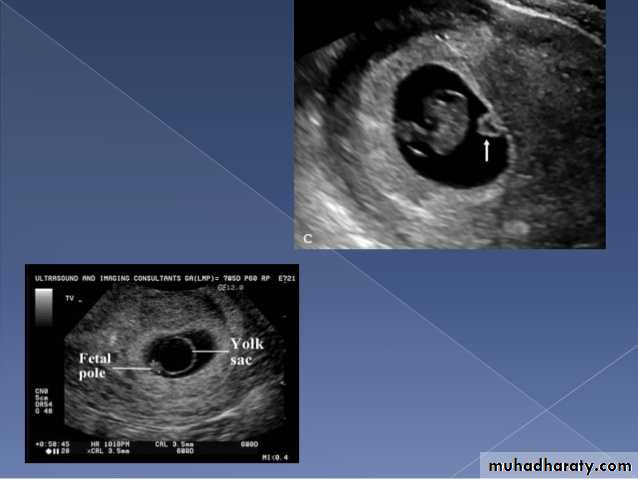

BPD together with head circumference (HC), abdominal circumference (AC), and femur length (FL) are computed to produce an estimate of fetal weight. In the second trimester this may be extrapolated to an estimate of gestational age and an estimated due date (EDD) .

The BPD should be measured on an axial plane that traverses the thalami, and cavum septum pellucidum. The transducer must be perpendicular to the central axis of the head, and thus the hemispheres and calvaria should appear symmetric.